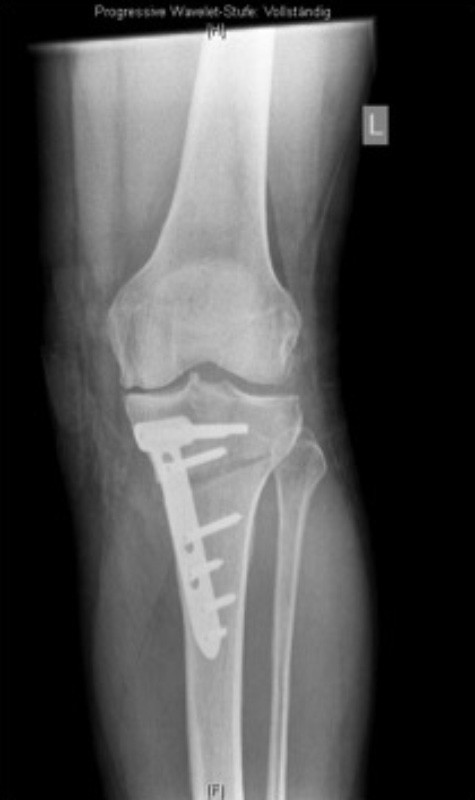

Kniegelenk nach operativer Korrektur einer O-Beinstellung

Kniegelenk nach operativer Korrektur einer O-Beinstellung mit noch einliegender Platte